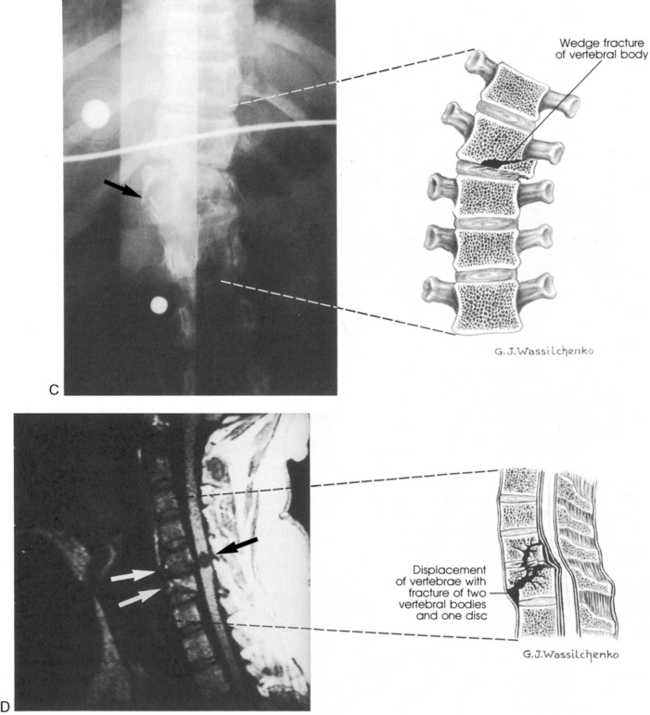

The cervical spine is relatively unstable and is still developing in young children. As a result, SCI patterns in children differ from those in adults. The ligaments along the child's cervical vertebrae are relatively lax, and the paraspinous muscles are incompletely developed. The child's vertebral bodies are wedge-shaped and not completely ossified. In addition, the facet joints of the cervical vertebrae are relatively flat. For these reasons, the vertebrae can shift several centimeters during injury or the application of force to the spine, resulting in spinal cord injury without evidence of injury to the vertebrae. Although the pediatric spine is relatively more elastic than the adult spine, it will be injured if significant cervical subluxation occurs (Fig. 11-19).

image image

Fig. 11-19 Spinal cord injury. Many injuries resulting in spinal cord damage produce visible radiographic changes, although a significant number (20%-60%) are not associated with any skeletal fracture or dislocation. A, Lateral cervical spine radiographs demonstrating skeletal abnormalities associated with cervical spine injury. The first radiograph is from a 4 year old who was restrained in a car seat that was not anchored in the car. The separation between the fifth and sixth cervical vertebrae is subtle but detectable (arrow), especially when compared with the line drawing of normal anatomy (far right). Radiopaque orogastric and nasogastric tubes are visible; they are slightly displaced anteriorly, indicating a small amount of edema surrounding the spinal cord injury. The location of the injury is unusual for this age. The second radiograph shows a 5-year-old pedestrian struck by an automobile and demonstrates significant separation between the first and second cervical vertebrae. This is a more common site of cervical spine injury in young children. Note the anterior displacement of the nasogastric tube (arrow) produced by edema surrounding the injury. An endotracheal tube is present but not visible. The line drawing depicts normal cervical spinal anatomy in a 3- to 4-year-old child. B, This scan film performed before a computed tomography scan demonstrates lumbar vertebral and spinal cord trauma associated with a lap belt injury. Separation of the lumbar vertebrae can be seen (arrow) and resulted in paraplegia. This injury resulted from flexion of the lumbar spine (see drawing). C, Flexion injury of the lower thoracic vertebrae and spine is visible on this anteroposterior chest radiograph. This radiograph shows an unrestrained 16-year-old driver who was thrown from the car. The lateral flexion resulted in compression of the spinal cord and fracture of the thoracic vertebrae (see arrow and corresponding illustration). The rod placed during surgery is visible. D, This magnetic resonance imagery scan shows in detail the skeletal and spinal damage resulting from a flexion-rotation injury. This 16-year-old motorcycle driver sustained displacement of two vertebrae (white arrows) and fracture of two vertebrae and one disc. Resulting compression of the cervical spine produced a complete spinal cord injury. A contusion is visible in the spinal cord (black arrow). The line drawing depicts the injury.

(A, courtesy Carol Gilbert and John Feldenzer, Roanoke, Va. Drawing reproduced from Riviello JJ, et al: Delayed cervical central cord syndrome after trivial trauma, Pediatr Emerg Care 6:116, 1990. B, courtesy Bennett Blumenkopf, Vanderbilt University Medical Center, Nashville, Tenn. Line drawing reproduced from Rudy EB: Advanced neurological and neurosurgical nursing, St Louis, 1984, Mosby. C, courtesy Noel Tulipan, Vanderbilt University Medical Center, Nashville, Tenn. Illustration reproduced from Rudy EB: Advanced neurological and neurosurgical nursing, St Louis, 1984, Mosby. D, courtesy Bennett Blumenkopf, Vanderbilt University, Nashville, Tenn. Line drawing reproduced from Rudy EB: Advanced neurological and neurosurgical nursing, St Louis, 1984, Mosby.)

The most common areas of SCI in children younger than 9 years include the atlas, axis, and upper cervical spine. Generally, ligamentous injuries are more common than bone injuries. In patients older than 9 years, injury patterns resemble those of the adult, with less cervical involvement.123

Pediatric spinal cord injuries occur when vertebral bodies are fractured, or when vertebral subluxation (partial dislocation) occurs. Subluxation results in anteroposterior misalignment of contiguous vertebrae, with narrowing of the spinal canal and spinal cord compression. Young children are likely to sustain subluxation injuries without associated fractures. The severity of the neurologic deficit is related to the location and severity of the subluxation.123

Diagnostic Studies

Good quality cervical and thoracic lateral and anteroposterior radiographs will enable the detection of many spinal cord injuries (see Fig. 11-19).123 A lateral radiograph is obtained that includes the first cervical vertebra to the first thoracic vertebra.6 Occasionally the lateral displacement of vertebrae will be apparent on the anteroposterior radiograph and may be noted on the chest radiograph. If the radiographs are equivocal, or if nonvisualized SCI is suspected, flexion-extension radiographs are obtained after the child is alert and responsive.50

A CT scan will allow definitive visualization of the upper cervical spinal column, soft tissue, and vertebrae.50 This examination should be part of the CT scan performed for every child with a severe closed head injury.